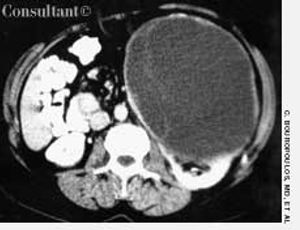

A 43-year-old woman was admitted to the hospital with left flank pain. The physical examination revealed a left abdominal mass. Laboratory test results identified normochromic-normocytic anemia (hematocrit, 33%; hemoglobin, 10.8 g/dL; and mean corpuscular volume, 88 fL) and microscopic hematuria (10 red blood cells per high-power field).